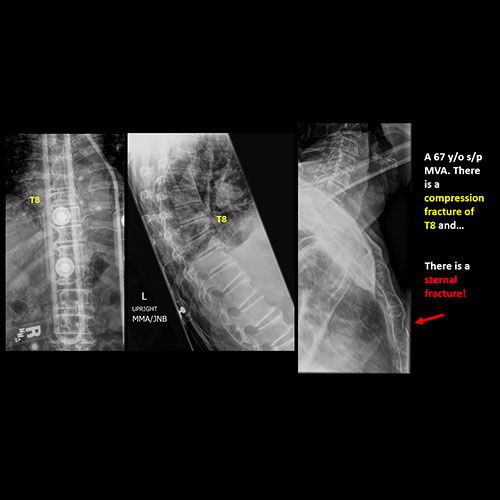

There is an endplate avulsion, compression, or other fracture. |

Yes | NA |

There is abnormality of the soft tissues and included bones of the upper extremities, clavicles, and sternum other than from degenerative change. |

No | NA |

There is an oblique fracture with avulsion through the anterior inferior T9 vertebral body. The posterior elements are intact. There is excessive calcification of the anterior longitudinal ligament and there are continuous osteophytes in a pattern consistent with DISH (Diffuse Idiopathic Skeletal Hyperostosis).

The findings were called to the referring physician and a CT scan is planned.